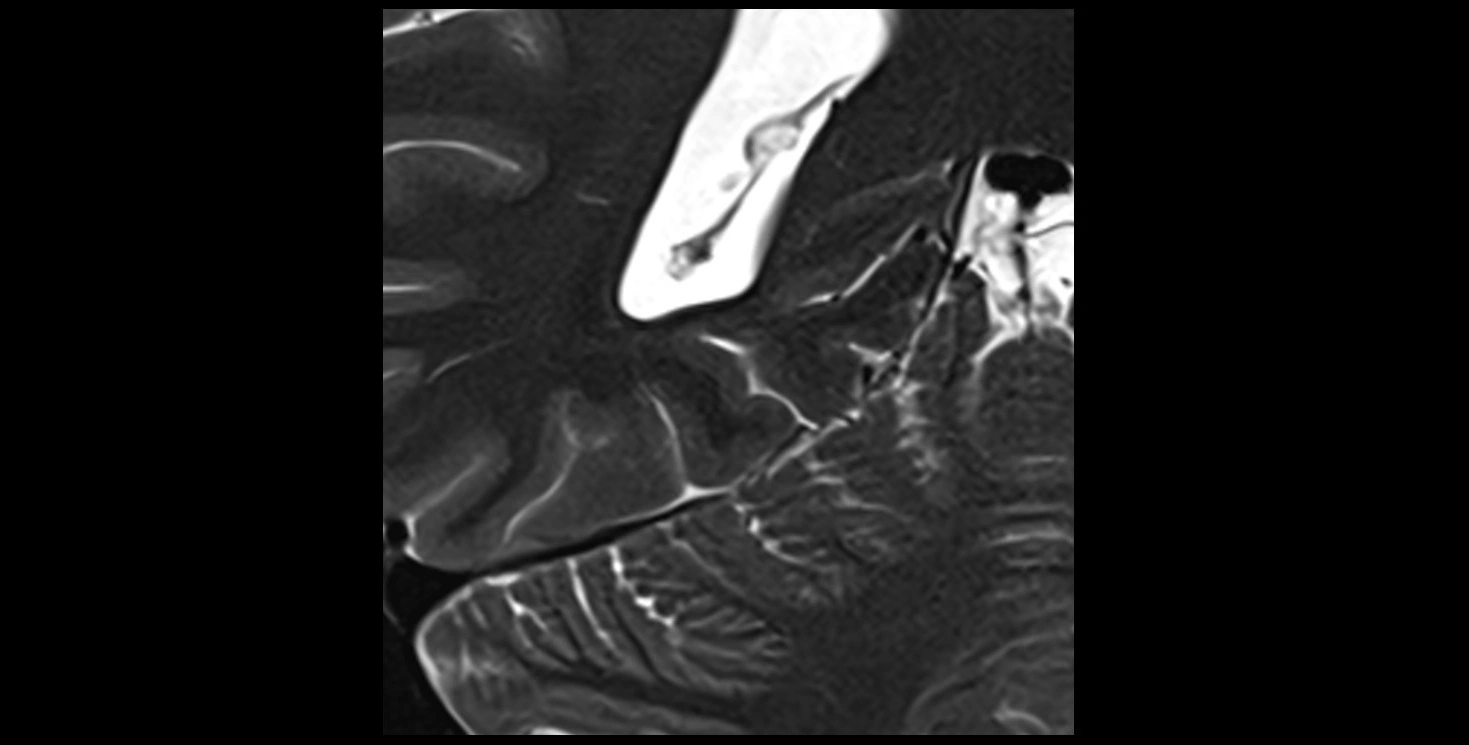

MRI images

image